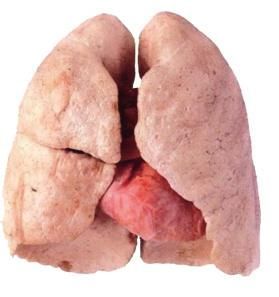

形態

胸廓前後徑增加,胸廓呈圓桶形,前後徑增大,或與左右徑大致相等,肋弓的前部上抬,肋骨呈水平位,肋間隙增寬飽滿,胸骨下角增大呈鈍角。叩診胸廓迴響增加,心濁音界縮小或消失,肝濁音界下降。呼吸音和語音均減弱,呼氣延長,有時兩肺底可聞及乾濕羅音。心音低遠。